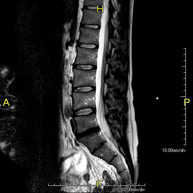

Prueba diagnóstica no invasiva que consiste en la obtención de imágenes de alta definición anatómica de la columna dorsal, mediante el empleo de un campo electromagnético y ondas de radio (con un emisor y un receptor). No utiliza radiación ionizante. Indicaciones: traumatismo, problemas degenerativos, hernias, tumores. - RM Columna lumbar

Prueba diagnóstica no invasiva que consiste en la obtención de imágenes de alta definición anatómica de la lumbar y sacra, mediante el empleo de un campo electromagnético y ondas de radio (con un emisor y un receptor). No utiliza radiación ionizante. Indicaciones: traumatismos, ciática, hernias discales, tumores, infecciones. - RM Mielografía